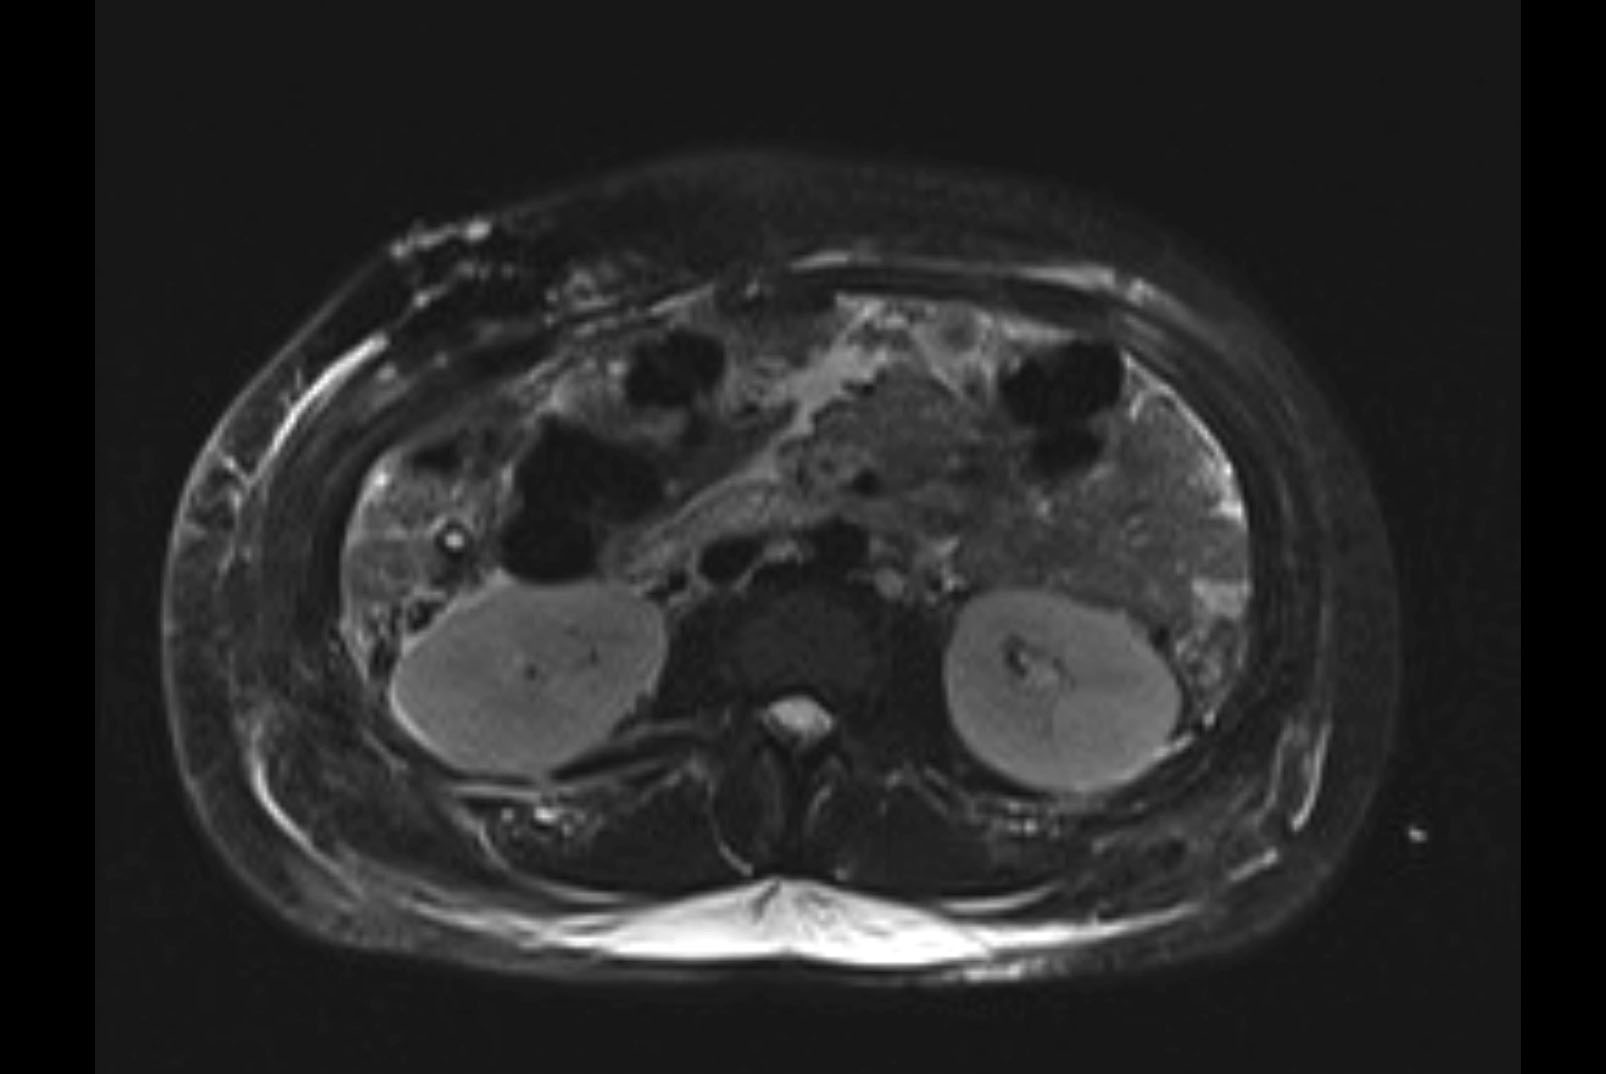

MRI T2